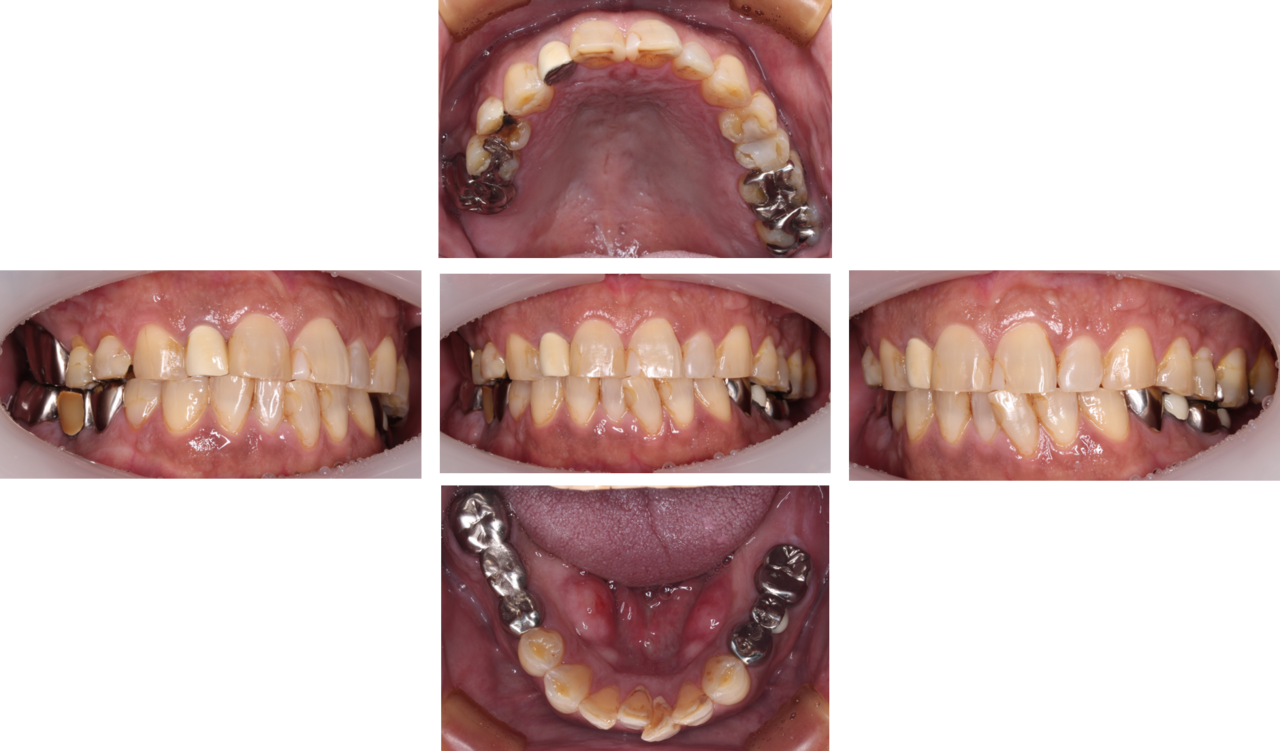

奥歯のインプラント症例③

治療前

治療後

治療内容

左側の奥歯3本の歯を失っており、かつ右側の奥歯のブリッジが破折していたため食べ物をうまく噛めないということでインプラント治療を行いました。

期間 4か月

費用 税込220万円

起こりうる副作用・リスク 保険外治療です。

手術後にインプラントの定期メンテナンスを怠ってしまうと、インプラント周囲炎になるリスクが高まります。